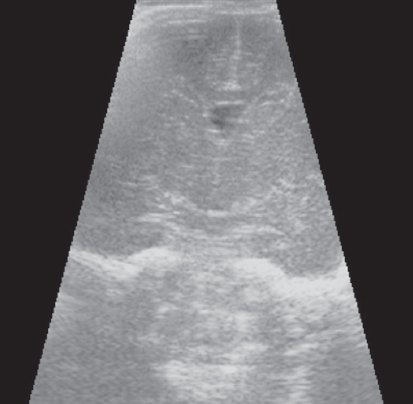

Краниальная сонография выполнена всем новорожденным (4 недоношенным новорожденным 25 недель гестации, 5 недоношенным 26 недель гестации, 3 недоношенным новорожденным 27, 28, 29 недель гестации) по общепринятой методике через большой родничок с использованием микроконвексного и линейного датчиков (5–7 Гц), аппарат Philips HD11 [14]. Методом КСГ проведено измерение визуализируемого гериминального матрикса в передних отделах боковых желудочков (проекция отверстия Монро), определяли толщину герминального матрикса, единицы измерения представлены в миллиметрах (мм) системы СИ (рис. 1).

Рис. 1. Краниальная сонография недоношенного новорожденного, 28 недель гестации, фронтальный скан. Стрелками указаны области визуализации герминального матрикса

Fig. 1. CUS image of preterm newborn, gestational age 28 wks., frontal scan. Arrows indicate the area of visualization of the germinal matrix